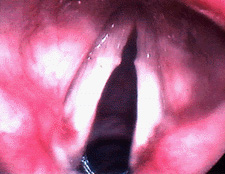

Close up of vocal fold nodule

The picture to the left shows typical vocal fold nodules. (Anterior is to the top, and posterior is the back. Note that they are present on both vocal folds and in this case are actually quite symmetric. The are located about one-third of the way back on the vocal folds.